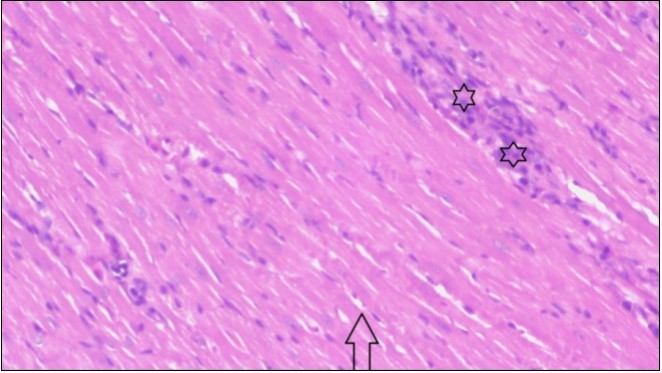

An important organ that is affected directly by the obesity which is the heart: The heart is the main important organ in circulatory system, the heart wall has three basic layers; the tunica intima of the heart is called endocardium, the tunica media of the heart is called the myocardium, the tunica adventitia of the heart the epicardium. The histological examination of the hearts of control rats feeding standard diet showing normal cardiac tissue with elongated, unbranched multinucleated muscle fibers (arrow), (Figure 1). The rats are feeding (HFD) for 2 weeks (obese rats) showing large number of inflammatory cells (star), degeneration muscles fiber ,circle and congested Blood vessels (arrow) (Figure 2). By comparison hearts of rats are treated by fennel after obesity and control rats observed show improved cardiac tissue with less infiltration (star) and well organized elongated muscle fibers with peripheral nuclei (arrow) (Figure 3). While examination of rats heart that treated by ator after obesity appears show less improved cardiac tissue with few inflammatory cells between disorganized muscle fiber (star), (Figure 4). While combined hearts of rats are treated by fennel and ator after obesity and control mice are showing nearly cardiac tissue with well-organized muscles fibers (arrow), (Figure 5).

Figure 3.Photomicrograph of heart section of treated rat with fennel herb showing improved cardiac tissue with less infiltration (star) and well organized elongated muscle fibers with peripheral nuclei (arrow), (H&E) (400X).

These results were confirmed with histological changes of feeding rats heart tissues with high fat diet only, which showed vaculation of tunica media and narrowing in the lumen of aorta sections as well as congestion of cardiac blood vessel and hyalinosis of its wall. This result was confirmed by Szilvassy et al., 78, who indicated that although hyperlipidemia increases oxidative stress in the cardiovascular system, it renders the heart and the vasculature more susceptible to stress. Ouwens et al. 79 identified that development of hyper-cholestremia, which is one of the risk factors for cardio vascular diseases is associated with increased blood levels of TC, LDL-C and VLDL-C as well as lowered levels of HDL in rats fed on high fat-diet. This result was confirmed by histological study, which revealed apparent normal histological structure of heart in all treated rats with fennel seeds. Epidemiologic studies have shown an inverse correlation between HDL-C level and the risk of cardiovascular disease. Increasing the HDL cholesterol level by 1mg may reduce the risk of cardiovascular disease by 2 to 3 percent 80. The present data agreed with Fatiha et al. 81, who reported that hyper-lipidemic rats treated with fennel extract had significant decrease in plasma levels of TL, TG, TC, LDL-C and VLDL, and significant increase in HDL-C level. The current study demonstrates that the alteration induced by high fat diet causing changes in blood parameters. These changes are exhibited through a decrease in RBCs, Ht, Hb and platelet and these changes could be due to oxidative stress, which lead to lipid peroxidation in RBCs membranes, auto oxidation of hemoglobin. As regards the total WBCs, lymphocytes and monocytes showed a marked decrease. While a distinct increase in the percentage of neutrophils and esinophils. The present, demonstrates that rats treated with (fennel), (ator) and (fennel with ator) exposure provided significant protection to the altered haematological variables. The effect of the treatment with fennel and ator is more effective than fennel only or ator only. The current study showed that the serum levels of the total protein and albumin in the obese group were significantly higher than those of the control group. The administration of (fennel) revealed significant decrease in the serum levels of the albumin and total protein as compared to the obesity group, although the serum levels of the albumin and total protein of the Ator group less than the obesity group. Otherwise, the levels of the total protein and albumin in fennel and Ator group were near to the similar value of the control group. The finding of this study indicates that the concentration of Malondialdehyde (MDA) and Myeloperoxidase (MPO) in liver homogenates of the fennel and ator group significant decrease than group (3) and group (4) and obesity group. There is a growing awareness that obesity is a prime risk factor for the development of dyslipidemia profile and that oxidative stress may play a role in various adverse effects of obesity.